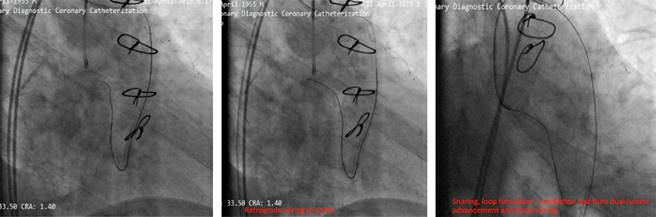

Our aim was to use the SVG as retrograde conduit for CTO PCI. During the procedure stenting was done but the stents balloon ruptured and made a huge dissection which caused a hematoma (Figure 4). As a bailout solution we decided to stent from the ostial LCx (Figure 5). To maintain a sufficient coronary perfusion, we decided to coil occlude due to Thrombolysis in Myocardial Infarction Score (TIMI) flow over 2 in this stenotic and thrombotic SVG so the competitive flow won’t affect the newly opened CTO’s long-term results. While coiling the donor SVG the coil dislodged. During the attempt to snare the dislodged coil with single loop snare, force by this device resulted in fracture in the dislodge coil and made two separated particles. One particle stayed in the descending aorta and the other went to the femoral artery. Both then were snared eventually (Figure 6).

Coil occlusion of SVGs is commonly employed to reduce competitive flow; however, in this case, coil dislodgement led to additional complications. The retrieval of coil fragments from both the descending aorta and femoral artery demonstrates the importance of having a bailout plan in such high-risk interventions.4

Moreover, the fracture of the coil during snaring highlights the need for careful handling of retrieval devices to avoid exacerbating complications.

Stenotic or occluded SVGs should be considered the primary retrograde route for CTO PCI when available, as they often lead to fewer complications and greater procedural success compared to other collateral routes. Coil retrieval, when necessary, is best managed with three-looped snares, which are superior to single-loop snares for preventing coil fracture and subsequent embolization. This case highlights the importance of careful procedural planning and the ability to handle unexpected complications during complex coronary interventions.